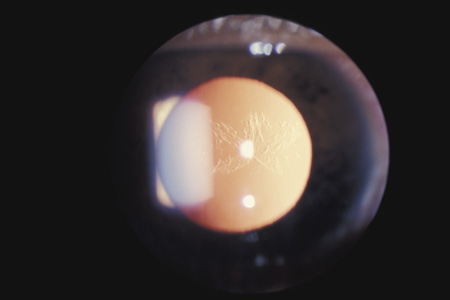

When the lens is struck by the cornea or by a strong shock wave, a transient anterior subcapsular cataract, known as a rosette cataract, may develop (Fig. 6). Repeated trauma, as in boxers, often causes posterior subcapsular cataract. Blunt trauma can also result in rupture of the anterior or posterior capsule.44,45 In severe cases, iridodonesis or a bead of vitreous in the anterior chamber signals a subluxed lens. Dislocation may also occur (Fig. 7). It is important to remember that ocular trauma is common, but lens dislocation is rare. Therefore, in patients with a dislocated lens, the clinician should always rule out predisposing causes such as Marfan's syndrome, homocystinuria and syphilis. In rare cases the lens itself can rupture and cause phacolytic glaucoma.

Fig. 6. An anterior subcapsular rosette cataract.